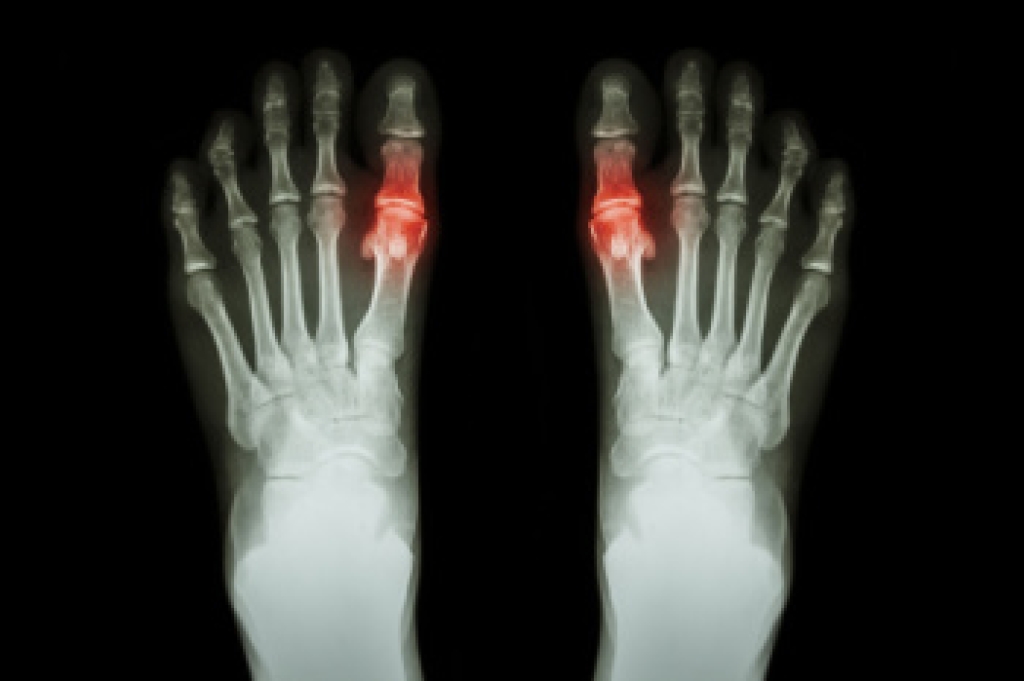

In many cases the cause of toe pain is obvious, but in others, a podiatrist may want to use more advanced methods to determine the problem. These can range from simple visual inspections and sensation tests to X-rays and MRI scans. Prior medical history, family medical history, and any recent physical traumatic events will all be taken into consideration for a proper diagnosis.

- Arthritis

- Gout